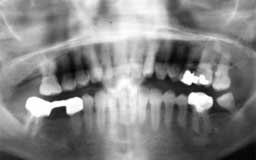

Yさん 初診時 54歳 女性

残存歯総数26本ですが、大量の歯石と上顎臼歯部の歯槽骨破壊が不気味です

Yさん 21年後 75歳

初診時以来歯を失うことなく順調に経過しています